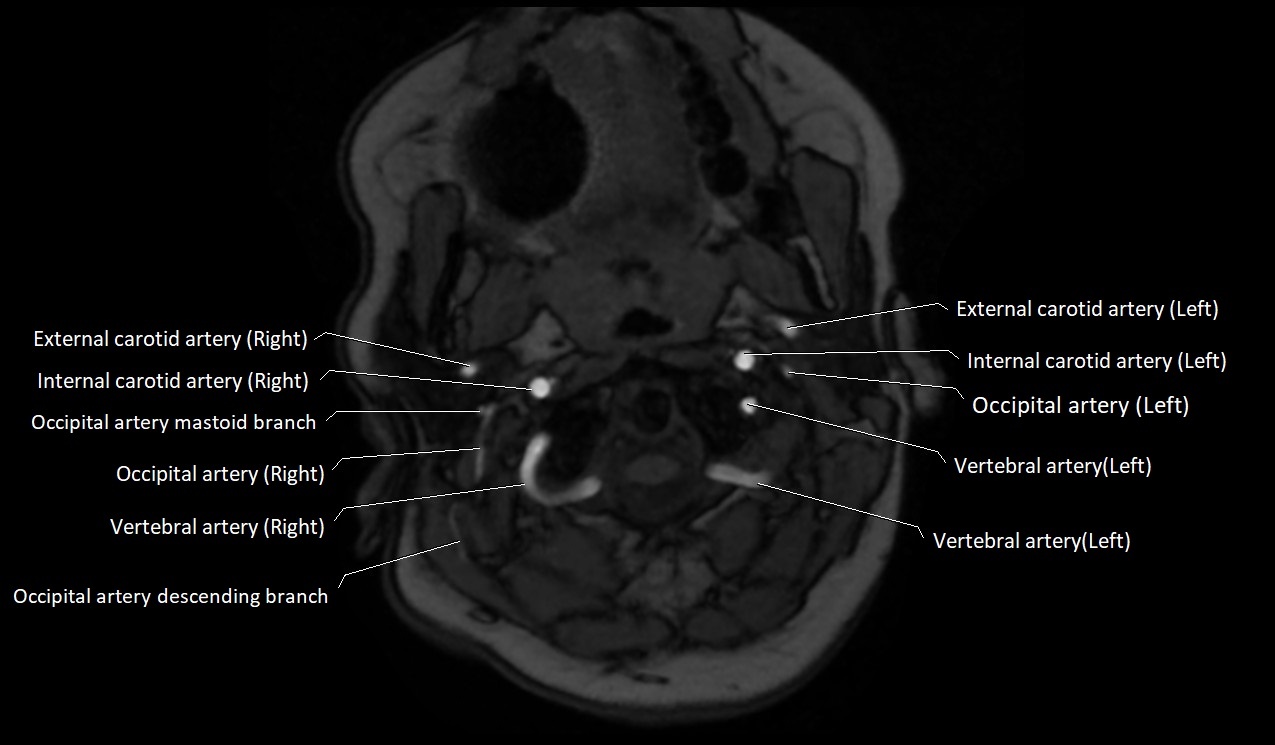

MRI Appearance:

• T1-Weighted Images:

• Appears as a tubular, hypointense (dark) structure relative to muscle

• May show flow void if the blood flow is fast

• T2-Weighted Images:

• Typically hypointense or isointense to muscle, but can be hyperintense if slow flow or stasis is present

MRI images